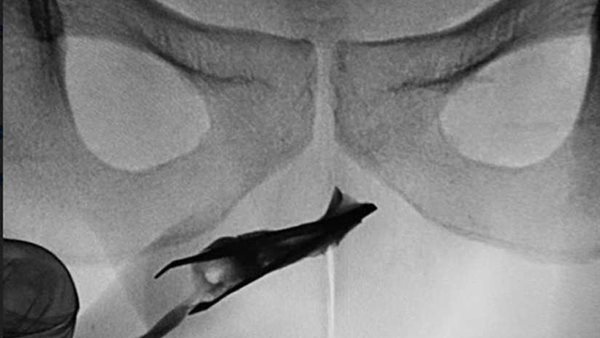

وحسبما ذكرت صحيفة "مترو" البريطانية، كشفت الأشعة السينية عن مكان وجود الملقاط ، الذي يظهر الطرف المغلق ، في مجرى البول بصلي في الأعلى.

وقام الأطباء ببذل جهود مضنية لإزالة "الملقاط" بالضغطً على جانبي القضيب لإخراج الملقاط الذى يبلغ حجمه 2.7 بوصة